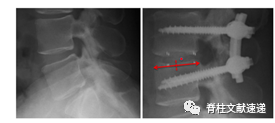

图注:上图为术后即刻X线片,下图为术后3个月X线片,可以看出该患者发生了术后cage移位(CM)。

图注:上图为术后即刻X线片,下图为术后3个月X线片,可以看出该患者术后3个月时cage移位到了椎管内,即发生了cage退回(CR)。